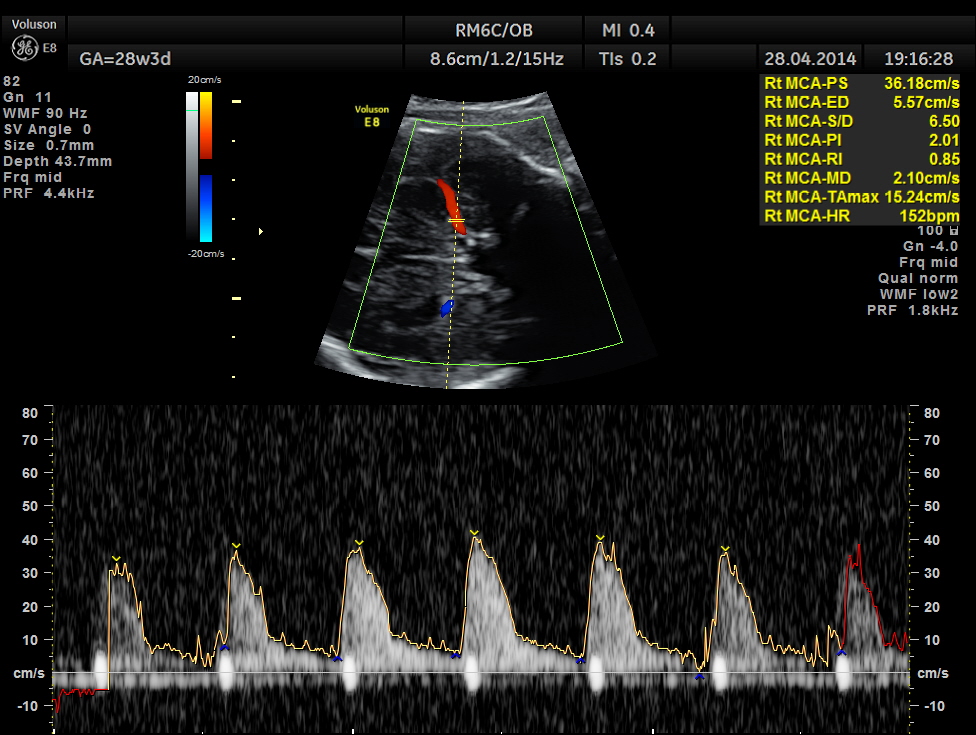

Spectral Doppler pictures are given below.

Umbilical arterial arterial P.I. and R.I. are high for the GA. and the cerebro placental ratio appears to be borderline > 1.0 and < 1.1 for the R.I.